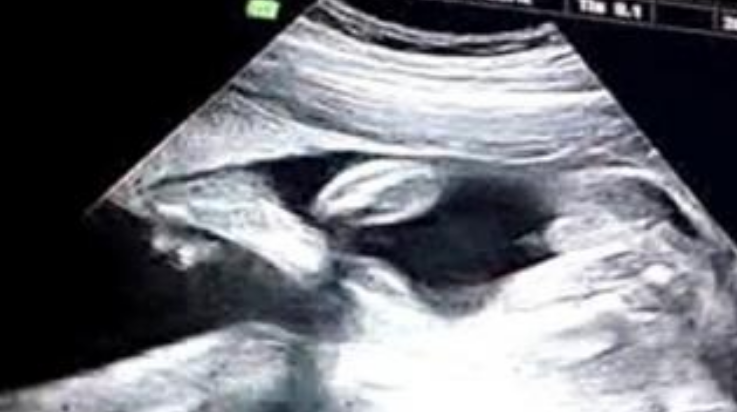

從b超單的形狀上看,如果是茄子或者長(zhǎng)條狀的男寶幾率大些,如果是圓圓鼓鼓的可能是女寶,還有看數(shù)據(jù),如果長(zhǎng)和寬的相差在一倍以上男寶寶可能性大,長(zhǎng)和寬相等女寶寶可能性大,B超顯示寶寶臉朝外的懷男孩,面對(duì)媽媽的懷女孩。